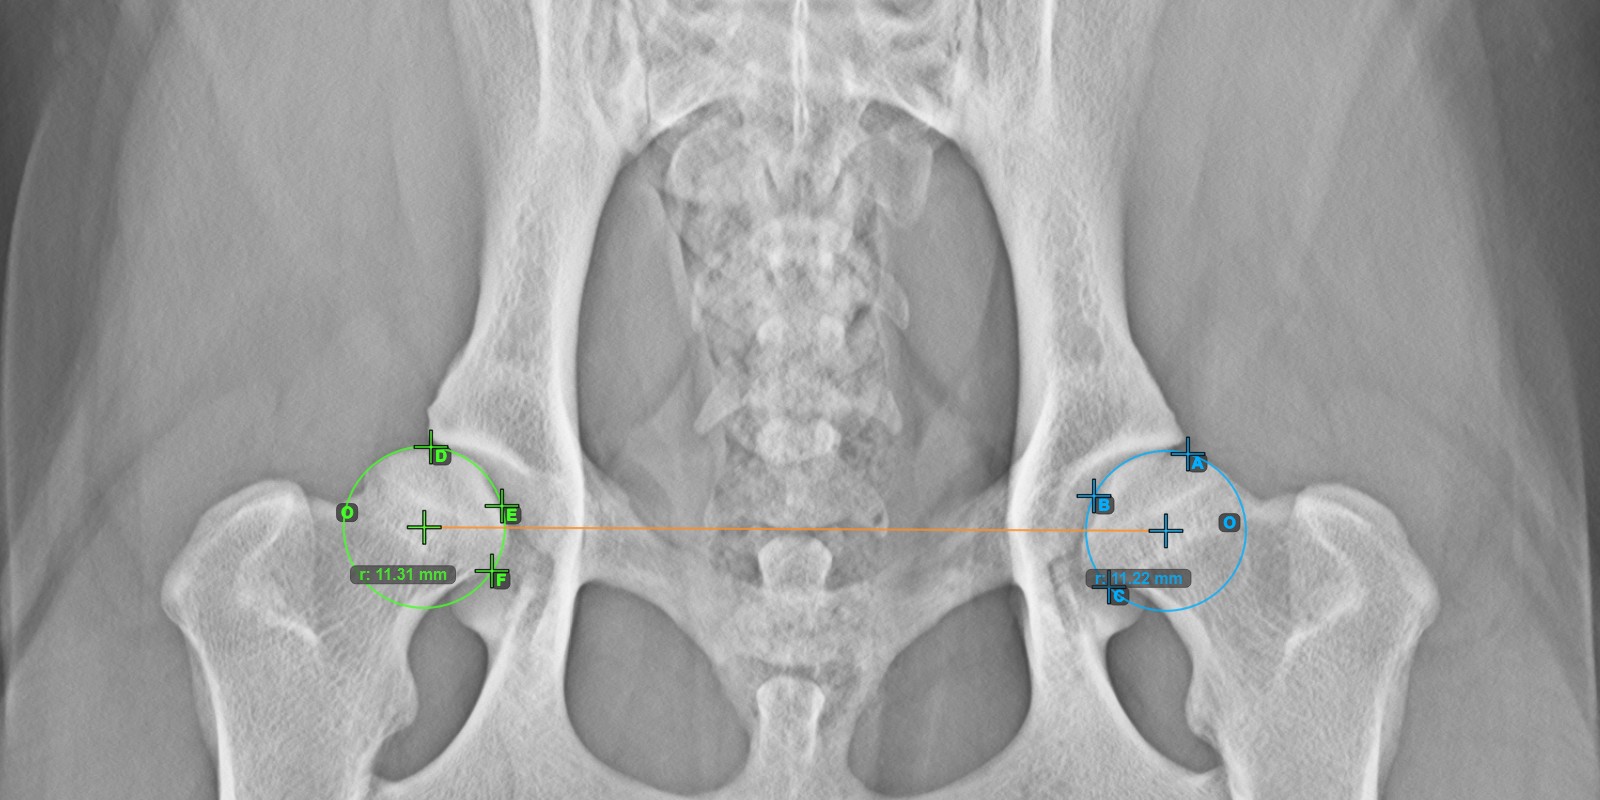

Start the measurement by marking the three points on the articular surface of the left Caput Femoris.

Mark the three points on the articular surface of the left Caput Femoris (outside of the Fovea Capitilis). Regardless of the order, make sure to mark the most cranial point, the most caudal point and the midpoint of the femoral head. A circle will be automatically constructed based on the three placed points.

The image below depicts the typical placement of the three points on the articular surface of the left Caput Femoris.

Continue by marking the three points on the articular surface of the right Caput Femoris.

Mark the three points on the articular surface of the right Caput Femoris (outside of the Fovea Capitilis). Regardless of the order, make sure to mark the most cranial point, the most caudal point and the midpoint of the femoral head. A circle will be automatically constructed based on the three placed points.

The origos of the two circles will also automatically be connected by a line, specifying the initial side of the angles yet to be constructed.

The image below depicts the typical placement of the three points on the articular surface of the right Caput Femoris.